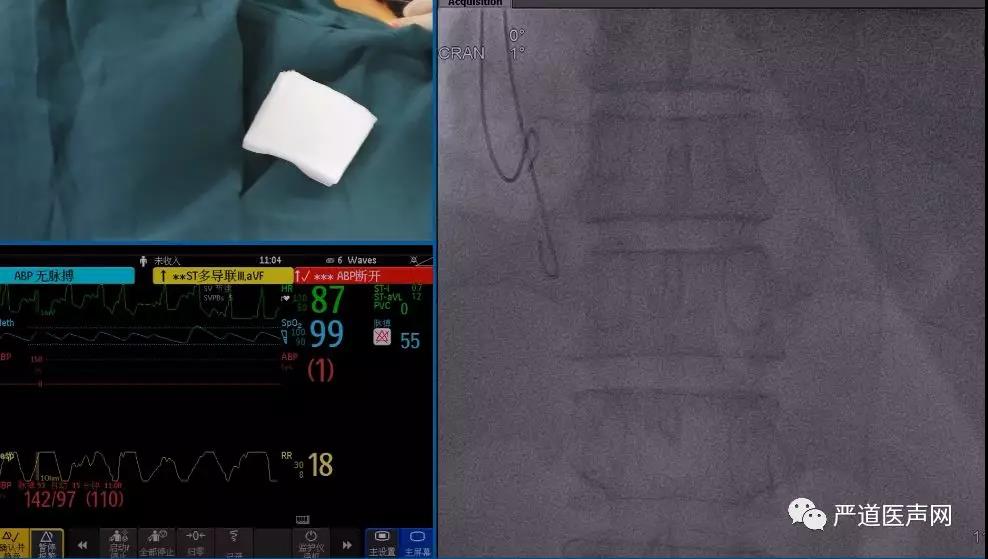

患者为男性,扩张性心肌病,术前评估心功能NYHAIII级,左室LVEF20%,CLBBB,QRS波宽度190ms,符合CRT-D植入I类指证。

穿锁骨下静脉。

放置右室除颤电极。